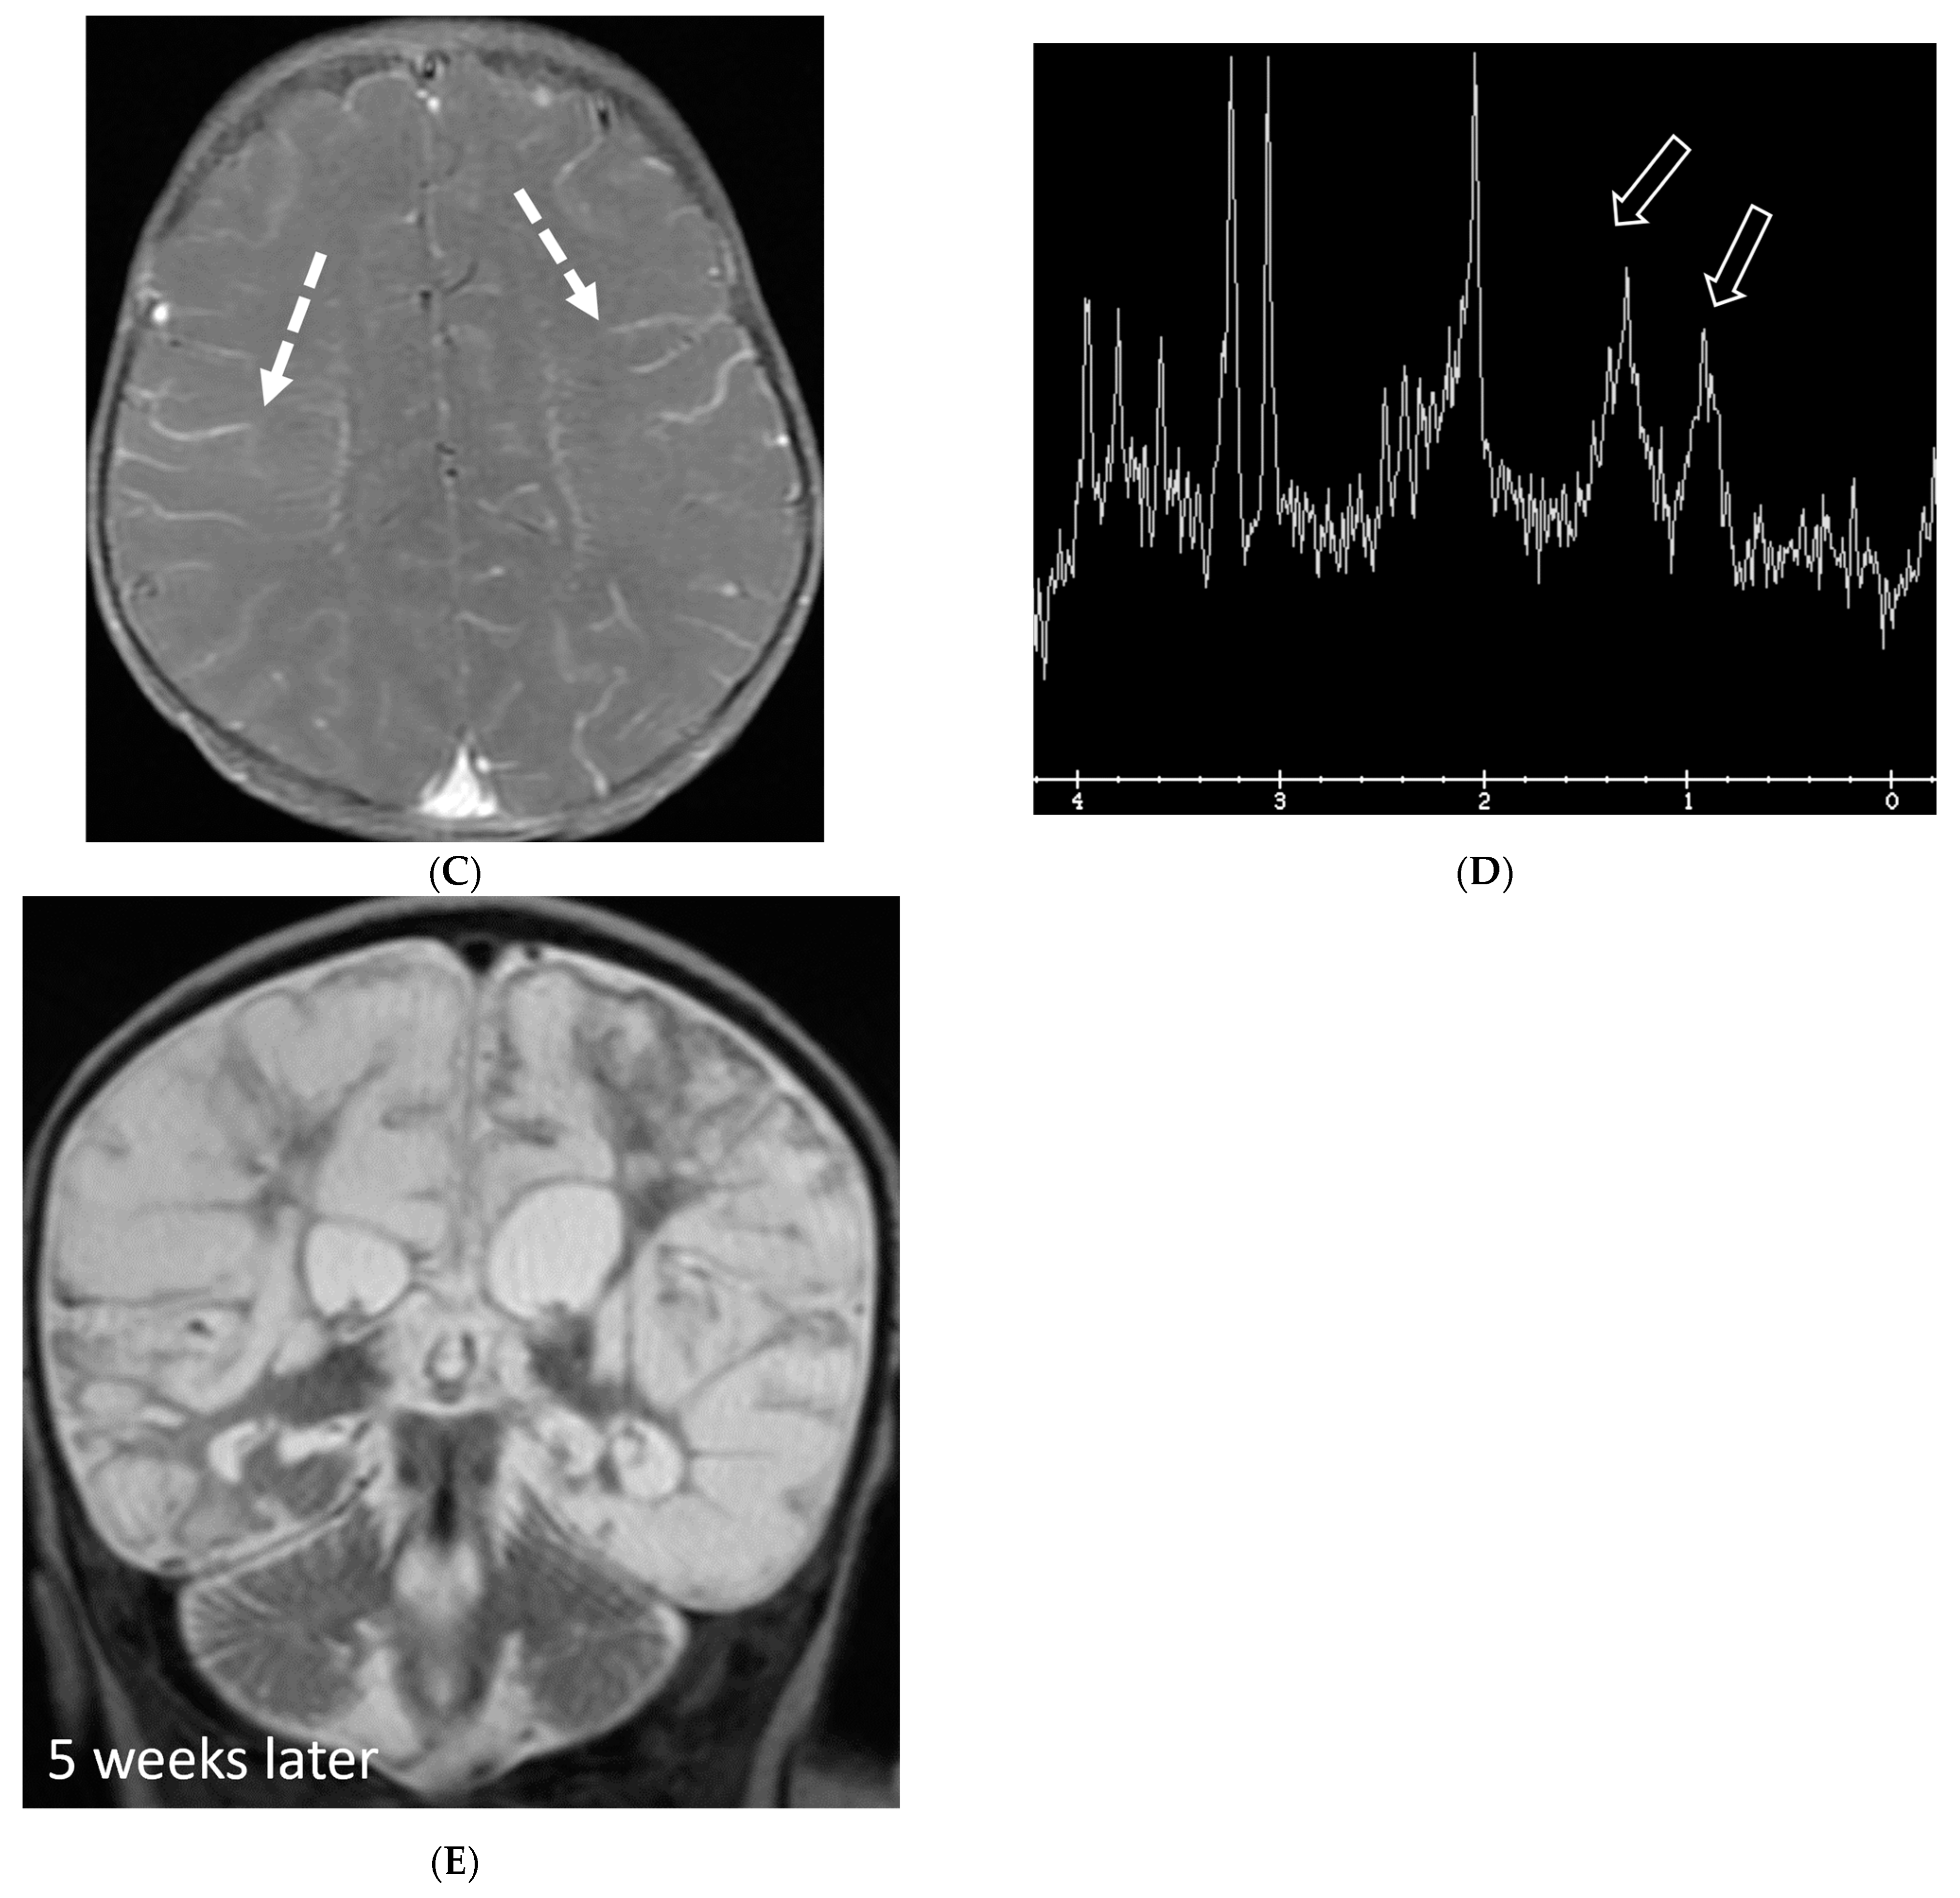

E. coli is another common neonatal and infantile cause of bacterial meningitis. There is characteristic diffusion restriction in the extra-axial collections along with ventriculomegaly and/or ventriculitis [74]. To note, extra-axial empyema is also common with S. pneumoniae, but occur in an older age group. Serratia marcescens and Citrobacter are two uncommon pathogens causing meningitis in neonates with fulminant disease course. They lead to large parenchymal abscesses with striated appearance on T2W images and foci of susceptibility. N. meningitidies causes typical gyriform cortical enhancement consistent with cerebritis predominantly involving the occipital lobes (Figure 12) [74].

Figure 12.

Axial DWI (A), axial SWI (B), sagittal T2 (C), axial ASL (D) and coronal T1 post contrast (E): 11-day-old female presented with seizures and lethargic. Restricted diffusion is noted in the sulci along the bilateral frontal convexities, concerning for meningitis (arrows). Curvilinear susceptibility in the extra-axial spaces of bilateral frontal convexities, consistent with thrombosed cortical veins (curved arrows). Cortical T2 hyperintensity is seen in the bilateral frontal and parietal lobes with corresponding hyperperfusion in keeping with extensive cerebritis (dashed arrows). Diffuse leptomeningeal and pachymeningeal enhancement is seen (open arrows). Overall features represent meningitis and cerebritis. Cerebrospinal fluid analysis: Group B streptococcus.